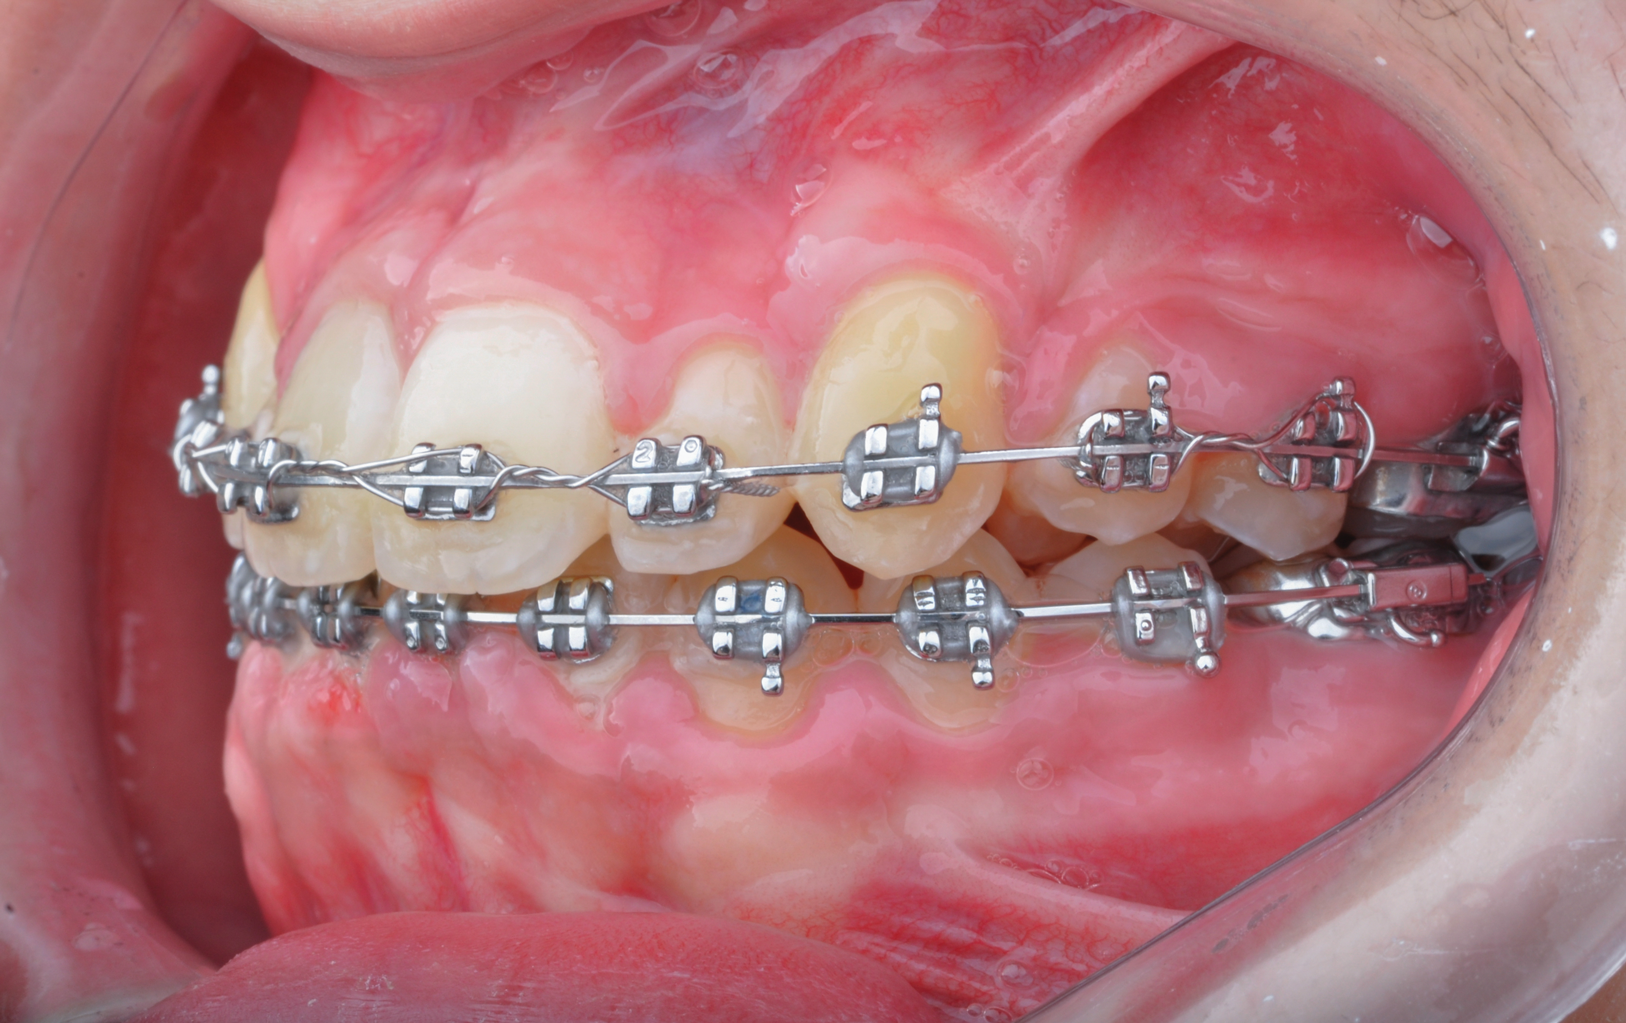

Fig 6. Use of apically positioned flap to manage bilateral facially impacted canines. During the same procedure a midline frenectomy was performed after the exposure and bilateral brackets were placed (Fig 6). Orthodontic traction was performed, which allowed both canines to be properly placed in the upper arch (Fig 7).

Figure 6

Fig 7. Use of apically positioned flap to manage bilateral facially impacted canines. During the same procedure a midline frenectomy was performed after the exposure and bilateral brackets were placed (Fig 6). Orthodontic traction was performed, which allowed both canines to be properly placed in the upper arch (Fig 7).

Figure 7